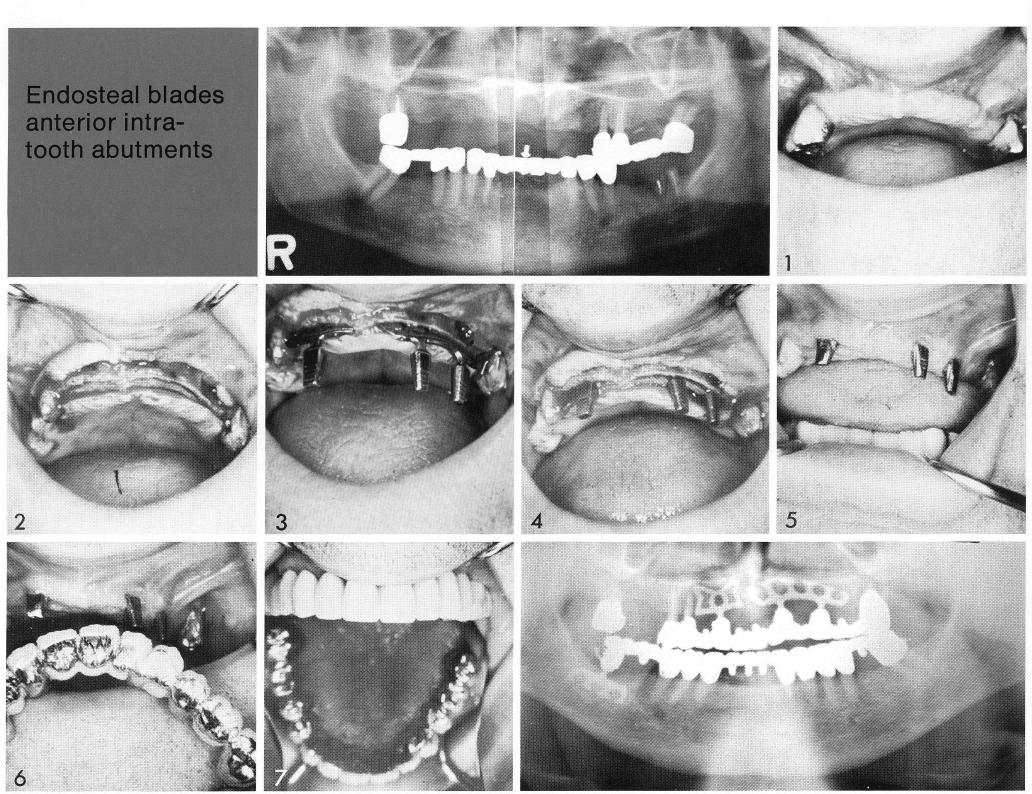

Endosteal blades anterior intra

tooth abutments

Narrowing of the maxillary ridge is typical of both partially (1) and totally edentulous patients, with one side of the ridge commonly more narrow than the other (2). Bladevents must often be acutely angled (3) and counter-sunk (4) in a narrow site. Note (3) that a double-posted bladevent is often the design of choice in a particularly narrow site to more evenly distribute pressure.

1 Narrow maxillary ridge for implantation